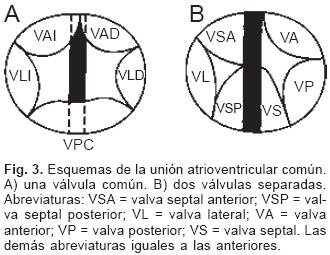

Sesenta y cinco corazones (92.86%) presentaron una válvula A–V dentro de un anillo fibroso A–V común (Fig. 3A) y los cinco restantes (7.14%) presentaron dos válvulas A–V separadas derecha e izquierda dentro del anillo fibroso común (Fig. 3B). La válvula A–V común estuvo constituida por cinco valvas, dos anterosuperiores derecha e izquierda, dos laterales derecha e izquierda y una posterior común; en estos corazones la CIV fue permeable (Fig. 2A), la distancia entre la unión A–V y el ápex estuvo disminuida y la distancia entre el ápex y la válvula aórtica aumentada (Fig. 4); la división entre ambos valores dio como resultado un cociente menor de uno.

De los sesenta y cinco corazones con válvula común en veinticinco se determinaron los tipos de la clasificación de Rastelli que fueron los siguientes: en once (44%) las valvas anterosuperiores derecha e izquierda se insertaron a través de sus cuerdas tendinosas sobre la cresta del tabique ventricular y la CIV se ubicó en los espacios intercordales (tipo A de Rastelli) (Figs. 1A y 5A). En un espécimen las valvas anterosu–periores izquierda (valva puente) y derecha se insertaron sobre la cara derecha del tabique ventricular por debajo de su cresta (Fig. 5B) y en otro dicha inserción se hizo en la parte superior del cuerpo de la trabécula septomarginal (Fig. 5C). En ocho corazones (32%) la inserción de esas valvas se estableció en un músculo papilar situado en la unión del tabique ventricular con la pared libre del ventrículo derecho y la valva anterosuperior izquierda pasó como puente por encima de la CIV (tipo B de Rastelli) (Figs. 1B y 5D) y en seis corazones (24%) la inserción de las valvas anterosuperior izquierda (valva puente) y derecha se insertaron en un músculo papilar de la pared libre del ventrículo derecho y esta valva se ubicó por encima de la CIV (tipo C de Rastelli) (Figs. 1C y 5E). En los cuarenta corazones restantes no fue posible determinar los tipos de Rastelli debido a que treinta y tres de ellos presentaron doble entrada ventricular (Fig. 6A) dos tuvieron modificaciones anatómicas generadas por la cirugía y cinco por presentar mutilaciones realizadas durante la necropsia. Los cinco especímenes con dos válvulas separadas tuvieron estructura trifoliada dentro de la unión A–V común (Figs. 3B y 6B); la válvula A–V izquierda mostró una valva lateral y dos septales anterior y posterior unidas a la cresta del tabique ventricular, lo que obliteró la CIV (Fig. 6C). La válvula A–V derecha mostró una valva septal displásica, una anterior y una posterior (Figs. 3B y 6B).

Se ha postulado que el defecto septal A–V es consecuencia de la falta de desarrollo y fusión de las almohadillas endocárdicas A–V dorsal y ventral, proceso anómalo que explica todas las alteraciones anatómicas presentes en esta cardiopatía.1,21 En vez de formarse dos anillos fibrosos como ocurre en el corazón normal se constituye uno común, dentro de él se forman dos válvulas A–V separadas o una válvula A–V común, lo que ha servido de base para la clasificación de esta cardiopatía congénita.2–4 Ambas formas tienen las mismas características patológicas básicas. Las dos válvulas separadas son de estructura trifoliada, la izquierda presenta 2 valvas septales anterior y posterior y una lateral, las valvas septales están separadas por una comisura que en el pasado se consideró erróneamente como una hendidura que según su extensión puede provocar insuficiencia valvular.23 Este concepto surgió debido a que la válvula A–V izquierda de esta cardiopatía se consideró homóloga de la válvula mitral del corazón normal, en realidad ambas son análogas, es decir cumplen una función similar pero tienen orígenes diferentes; ya se mencionó que en el corazón normal la valva medial de la válvula mitral deriva preponderantemente del componente izquierdo del tabique A–V doblado mientras que en esta cardiopatía la válvula A–V izquierda se origina de un nivel más inferior a partir del mesénquima que circunda el canal A–V común. En rigor en esta cardiopatía la válvula A–V izquierda no debe llamarse mitral, ya que su constitución es trifoliada, por lo que es preferible denominarla válvula A–V izquierda; las valvas septales de ésta se unen de manera continua a la cresta del tabique ventricular, con lo que queda obliterada la CIV perimembranosa y de entrada. Este hecho es determinante del establecimiento del cortocircuito por encima de las valvas A–V; el espacio entre éstas y el borde inferior del tabique interatrial comúnmente se ha considerado como FP, que en realidad es la suma del DSA–V y del FP; cuando éste está presente el borde inferior del tabique interatrial es cóncavo y queda por encima del plano del anillo fibroso A–V. Se han descrito casos en que dicho borde inferior no es cóncavo sino recto y coincide con el plano A–V, situación en la que está ausente el FP y el cortocircuito interatrial se establece a nivel del defecto septal A–V.2,9 Cuando se desarrolla una válvula A–V común con su patrón de cinco valvas, la gran comunicación permanece permeable.1,2,16,21